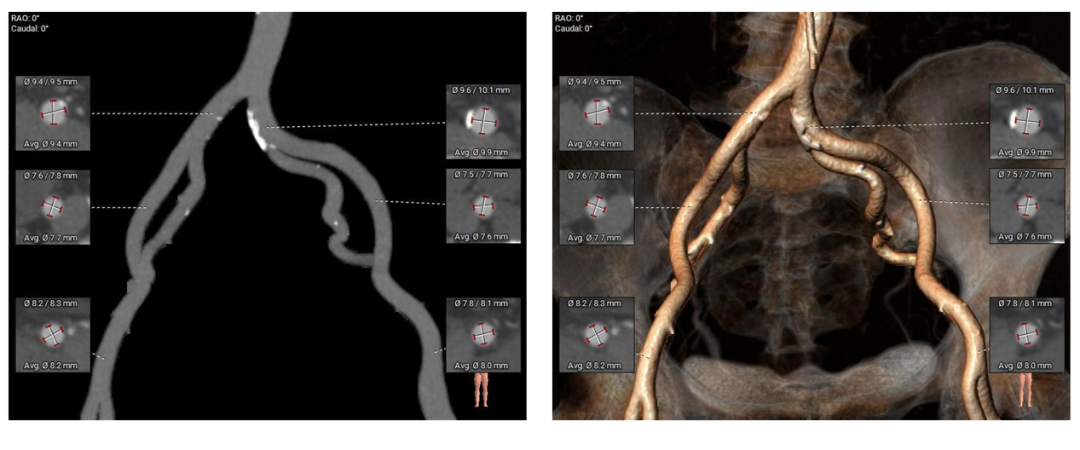

外周入路

Type-0型二叶瓣,中-重度钙化伴瓣叶增厚,左冠开口高度偏低,右冠开口高度可,左冠瓣叶长度略大于冠脉开口上缘与瓣叶附着缘距离,左室流出道整体呈直筒型,瓦氏窦,窦管交界,升主动脉内径可,左室腔内径可,心室壁增厚,主动脉瓣环与水平面夹角51度,非横位心,主动脉弓距、弓角可 -双侧入路血管走形良好,整体入路条件可

使用沛嘉20mm球囊预扩,预装沛嘉TaurusElite AV23瓣膜,释放高度瓣上0-2mm